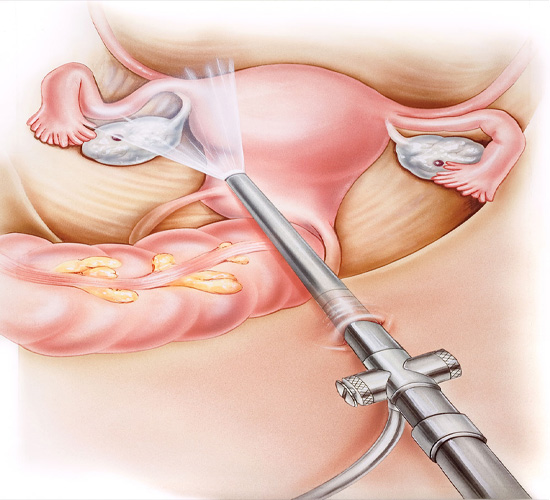

Laparoscopy

Laparoscopy is a keyhole surgical procedure used to diagnose and treat infertility-related conditions like endometriosis, fibroids, and ovarian cysts.